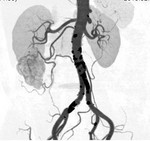

[画像診断]精巣・卵巣動脈の分岐について 2010-07-15